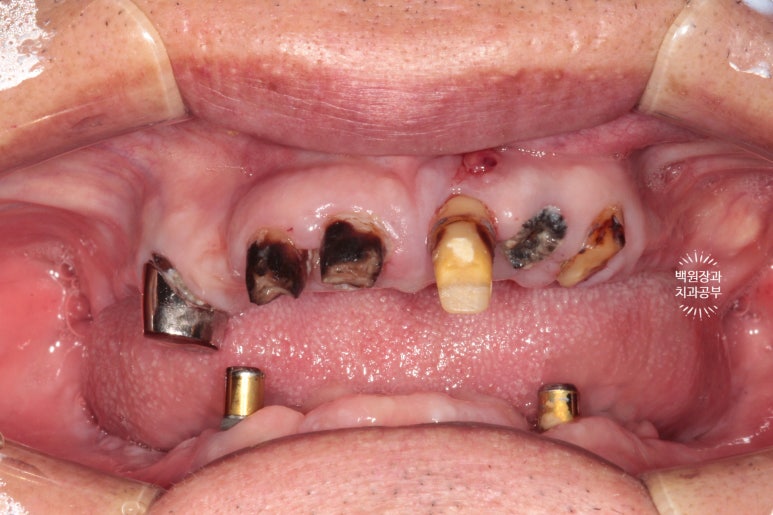

뿌리만 남은 치아가 많아요.

그런데 위 앞니 보철물이 이차충치로 인해 떨어져 나가게 되면서 보니 충치가 심해서 뿌리만 남았더라구요..

보시다시피 상태가 좀 심각했습니다.

그리고 왼쪽 사진을 보시면, 회색의 무언가가 보이실텐데...

잇몸뼈 안에 있어야할 임플란트가 주변의 뼈가 녹아 없어지면서 드러나 있는 상태였어요.

위턱을 보시면 정말로 뿌리만 있는 치아를 보실 수 있어요.

다만, 남은 잇몸뼈들은 상대적으로 건전하여 틀니를 하기에는 무리가 없어 보였습니다.

아래는 임플란트 2개를 이용한 임플란트 틀니 (=오버덴쳐)를 사용중이셨는데요,

왼쪽 임플란트는 이미 잇몸 밖으로 임플란트의 일부가 드러나 있었어요.

임플란트 주위염이라고 부르는데요~ 상태가 심각하여 제거해야하는 수준이었습니다.

비교적 오른쪽 임플란트는 낫군요..